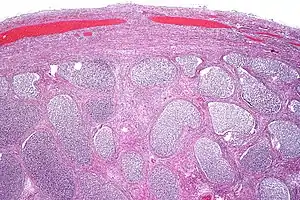

Acute epididymitis with abundant fibrinopurulent exudate in the tubules. | |